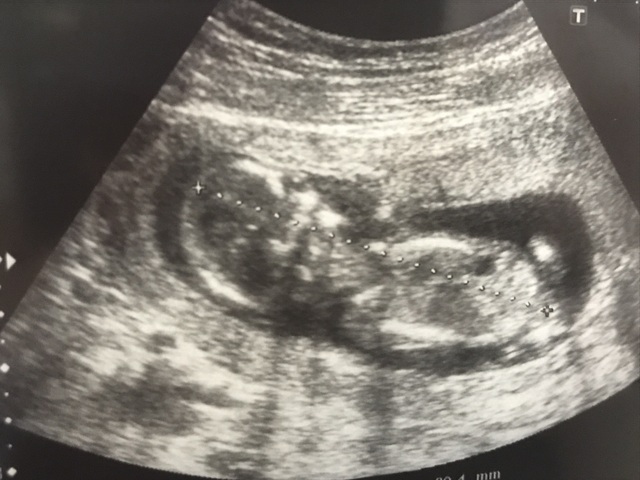

14週4日(14w4d・男の子)|あおい さん(27歳)

エコー写真撮影時のエピソード:

初めて4Dで写してもらいました。 顔が写ってくれたらいいな~と思いましたが完全に後ろ向き…

ですがこの姿勢は正座!

その場にいた先生みんな爆笑!この時先生には骨格を褒められ足が長く背の高い子に育つね!と言われうれしくなりました。